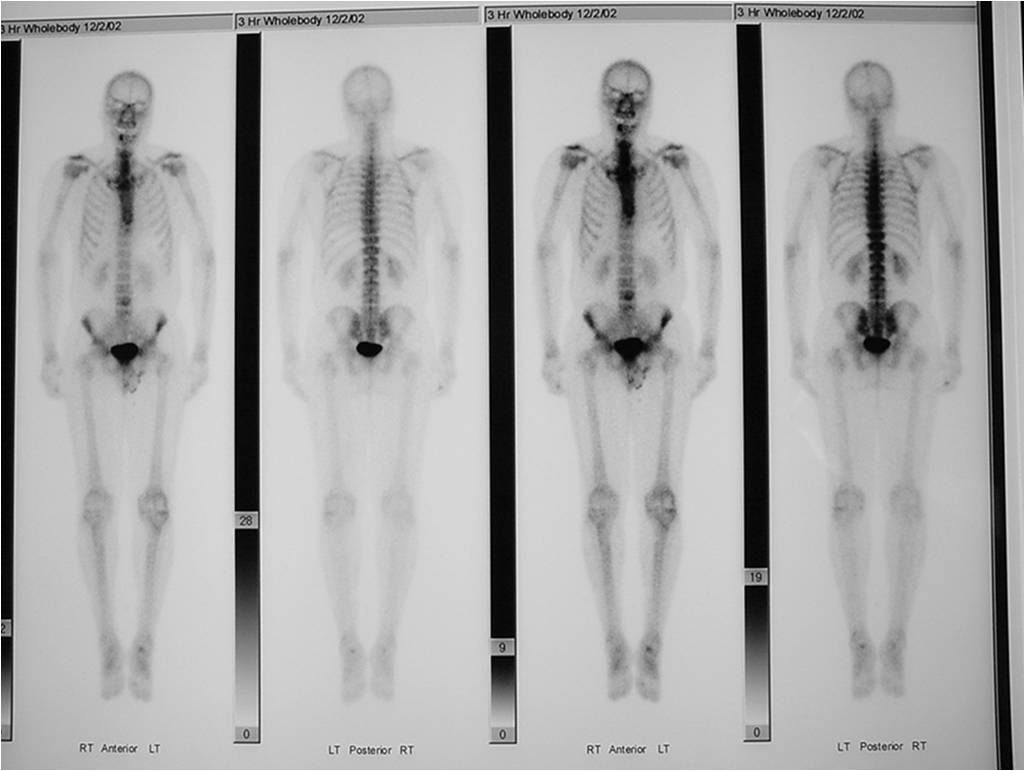

- Bone Scan: Lesion that is hotter than ASIS

- Features consistent with chondrosarcoma

- Pain attributable to lesion

- Age greater than 50

- Cortical destruction and a soft tissue mass

- Periosteal reaction and thickening

- Endosteal erosion>2/3 cortical thickness on a CT scan

- Size greater than 5 cm